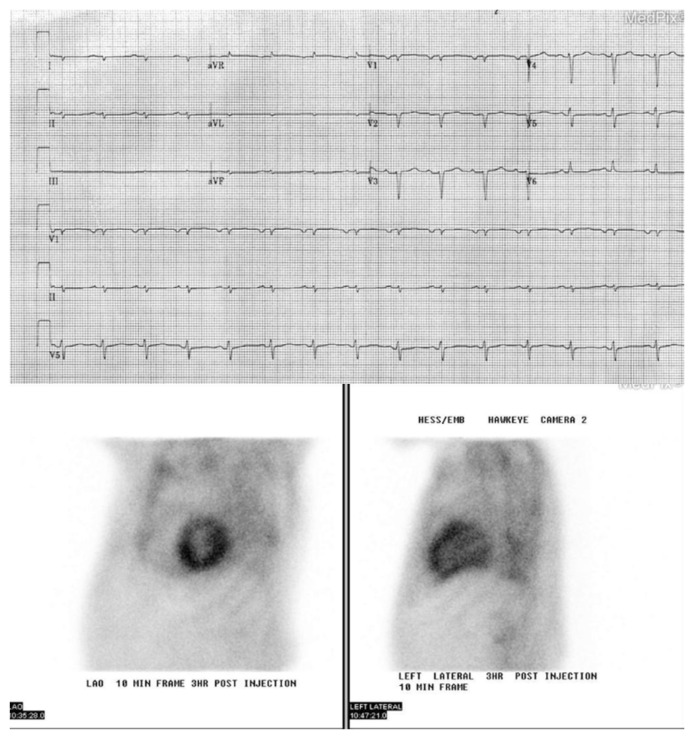

转甲状腺素淀粉样心肌病(atr - cm)是由转甲状腺素淀粉样原纤维在心肌中积累引起的,这是野生型或变异型转甲状腺素蛋白不稳定和错误折叠的结果。老年心衰患者在没有高血压或其他已知原因的情况下,超声心动图显示心肌壁厚升高和舒张功能不全,应怀疑atr - cm。心脏MRI晚期钆增强显示心肌细胞外体积(ECV)升高,提示淀粉样蛋白沉积导致间质空间扩张,进一步支持了这一诊断。诊断工作从血液和尿液检查开始,以排除AL淀粉样变性和未确定意义的单克隆伽玛病(MGUS),随后用Tc-99m示踪剂进行核闪烁成像,在单光子发射计算机断层扫描(SPECT)上显示心肌相对示踪剂摄取增加。转甲状腺素(TTR)基因的基因检测确定野生型或变异型ATTR淀粉样变。Tafamidis是一种TTR蛋白稳定剂,是目前唯一被批准用于治疗ATTR心肌病的疾病改善疗法。atr - cm的管理还包括心力衰竭、心律失常和心脏传导阻滞。

Transthyretin amyloid cardiomyopathy (ATTR-CM) arises from the accumulation of transthyretin amyloid fibrils in the myocardium, a consequence of instability and misfolding in wild-type or variant transthyretin protein. ATTR-CM should be suspected in older heart failure patients with raised myocardial wall thickness and diastolic dysfunction on echocardiography in the absence of hypertension or other known causes. This diagnosis can be further supported with late gadolinium enhancement on Cardiac MRI which indicates raised myocardial extracellular volume (ECV) hinting at the expansion of interstitial space by amyloid deposits. Diagnostic work up starts with blood and urine tests to rule out AL amyloidosis and monoclonal gammopathy of undetermined significance (MGUS) followed up by nuclear scintigraphy with Tc-99m tracer which shows increased relative tracer uptake by the myocardium on Single-photon emission computed tomography (SPECT). Genetic testing of the transthyretin (TTR) gene determines wild or variant type of ATTR amyloidosis. Tafamidis, a TTR protein stabilizer, is currently the sole approved disease-modifying therapy for ATTR cardiomyopathy. Management of ATTR-CM also involves managing heart failure, arrhythmias, and heart blocks.